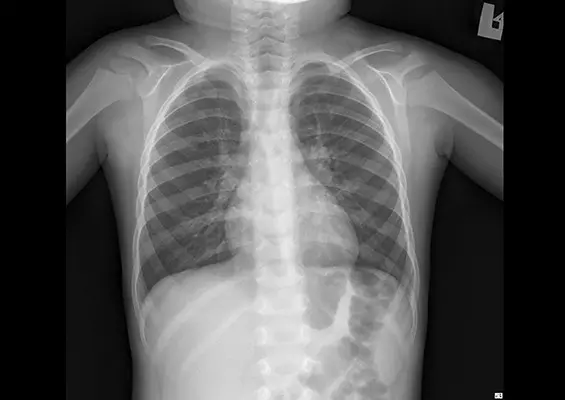

STUDIUM PRZYPADKU

- Kinga Szczepańska , Jarosław Mijas

- 15 grudnia 2020